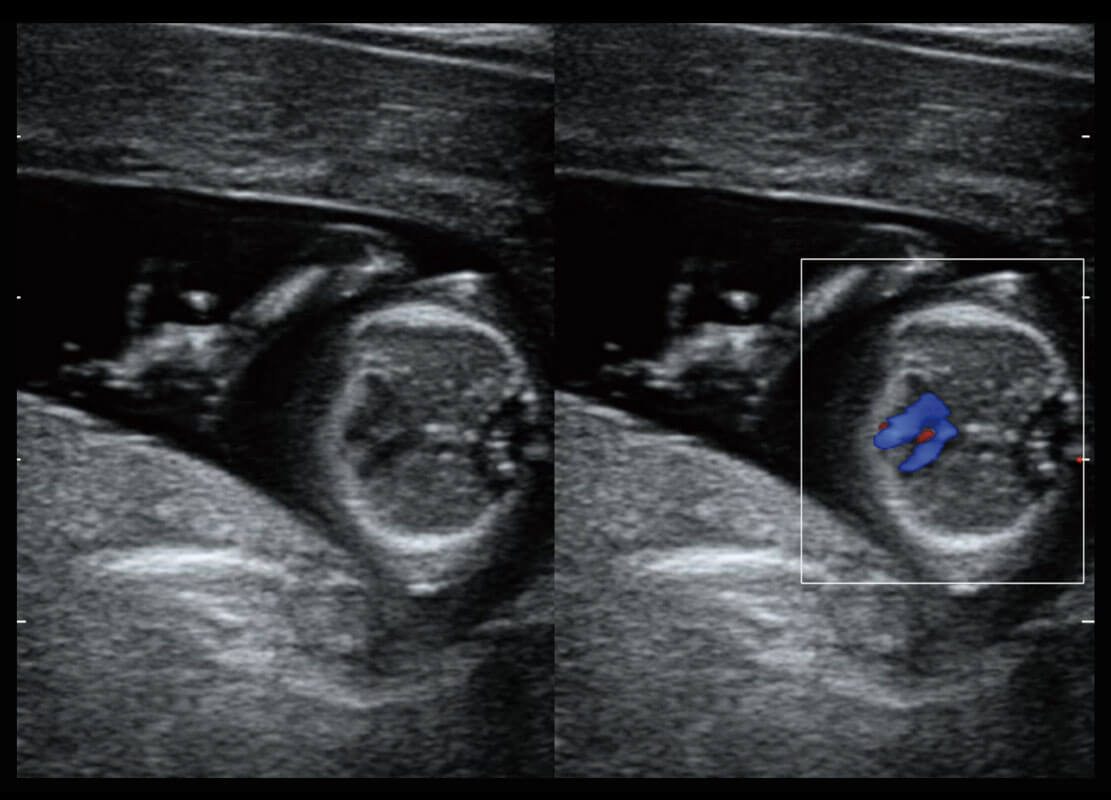

P60在胎儿早孕期超声筛查中为您带来优异的图像质量。

早孕-胎心

高分辨率容积成像-早孕胎儿

胎儿体循环

光影成像-孕囊